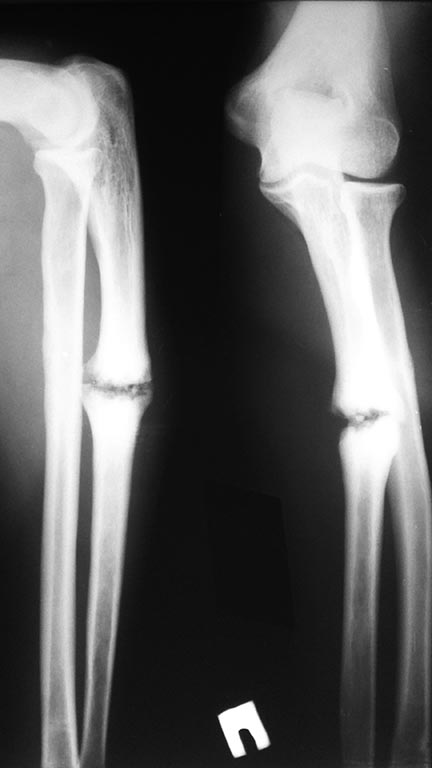

[Ortho] Ложный сустав локтевой кости

Пациент 30 лет, социально адаптированный, травма год назад, не

лечился.На данный момент беспокоит только деформация предплечья (языком

пациента шишка на руке), планирую выполнить резекцию ложного сустава,

остеосинтез пластиной с костной пластикой.Интересно послушать мнение коллег.